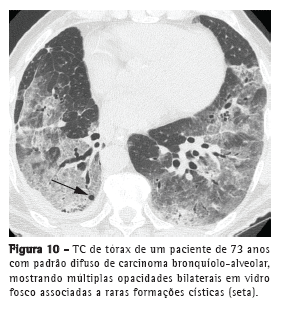

O envolvimento difuso do CBA pode representar origem multifocal, disseminação endobrônquica, metástases hematogênicas ou combinações desses padrões. Consolidação, nódulos (Figura 9), opacidades em vidro fosco, broncogramas aéreos e cistos (Figura 10), assim como distribuição periférica e nos lobos inferiores, caracterizam esse padrão.(20) Lesões pulmonares satélites podem ser vistas tanto no CBA, quanto na pneumonia.(18)